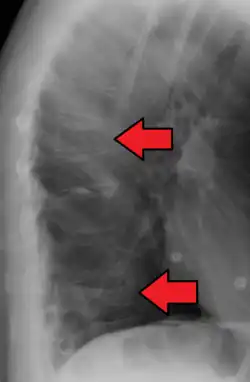

Compression fractures are usually diagnosed on spinal radiographs, where a wedge-shaped vertebra may be visible or there may be loss of height of the vertebra. In addition, bone density measurement may be performed to evaluate for osteoporosis. When a tumor is suspected as the underlying cause, or the fracture was caused by severe trauma, CT or MRI scans may be performed.

Compression fracture of T12